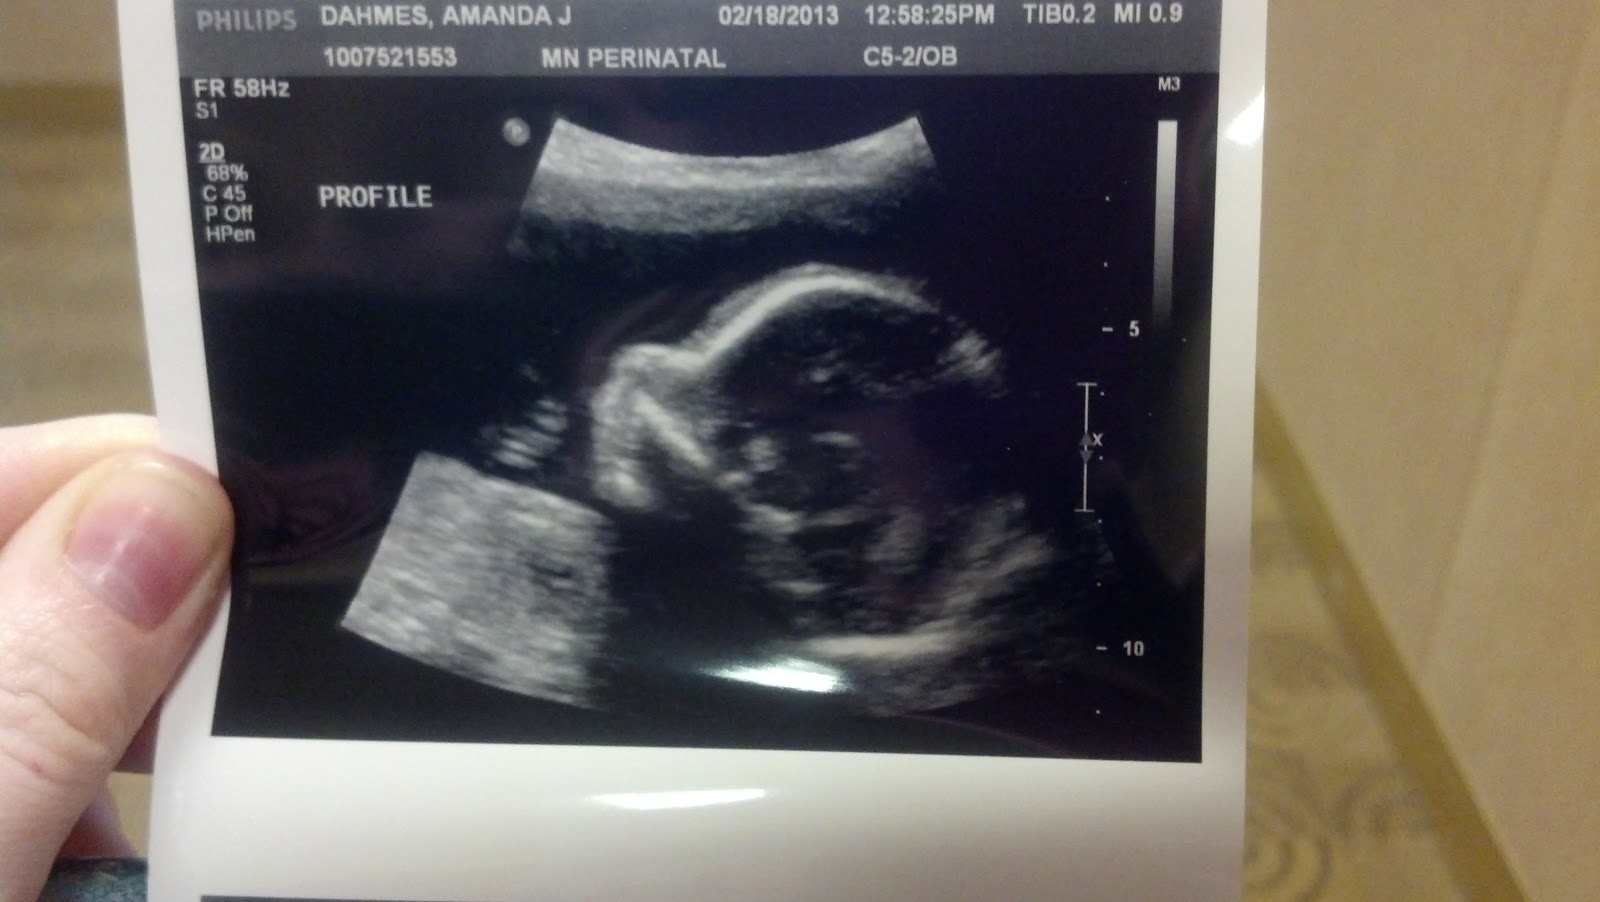

20 week ultrasound

well today I headed to St Cloud for our 20 weeks level 2 ultrasound. The weather was bad up north so Sam and her Mom couldnt make it. It really sucked not having her there and I honestly can say Im over winter even more so now. I couldnt of been a surrogate for anyone that lived far away and couldnt come to as many appointments as possible. I am happy to say that little man is doing great. Hes as the 63% tile and if he stays at about this point he will be 8 plus lbs. His heart brain and spine all looked beautiful. He was a mover thats for sure. Took a while longer then usual to get all the measurements they needed. They want me to go back around 30 weeks to check my fluid to make sure there is no repeat of my sons pregnancy (lost water at the end of pregnancy and had to be induced).